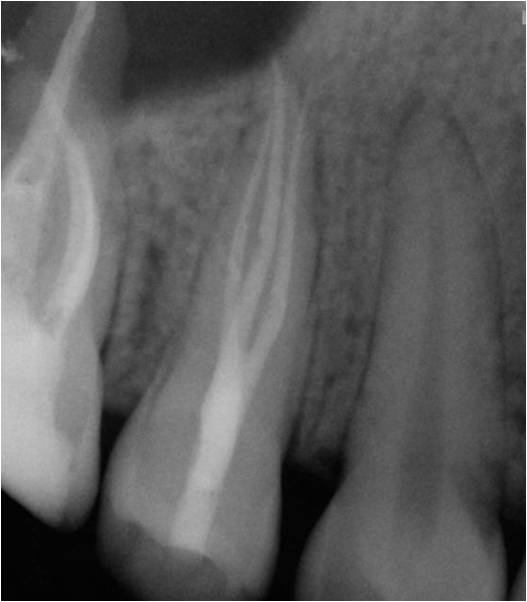

Excellent diagnosis essentially begins with two fundamental components: a doctor willing to listen to the patient’s chief complaint, and proper diagnostic tools. Among the most important tools are a precise periapical radiograph (PA) and bitewing (BW). Although a PA is often enough to provide an accurate portrayal of the patient’s condition, sometimes it alone does not suffice. Figure 1, Figure 2, and Figure 3 demonstrate a case that illustrates this point clearly. Despite two acceptable PAs (Figure 1 and Figure 2), it is difficult to assess the source of the patient’s pain to temperature. However, the BW radiograph Figure 3 provides significantly more clarity than either of the two PAs. The BW depicts localized bone loss (around tooth No. 2), a pulp stone (No. 2), a flat occlusion, numerous calcified canals, multiple restorations in tooth No. 30, and gross decay especially on tooth No. 3, which is the source of the patient’s pain to temperature. In this instance these images depict how much more useful a BW can be than just a conventional PA.